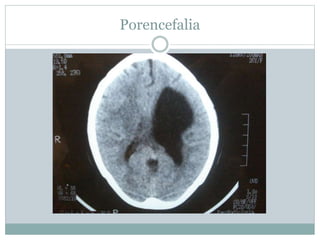

Porencefalia